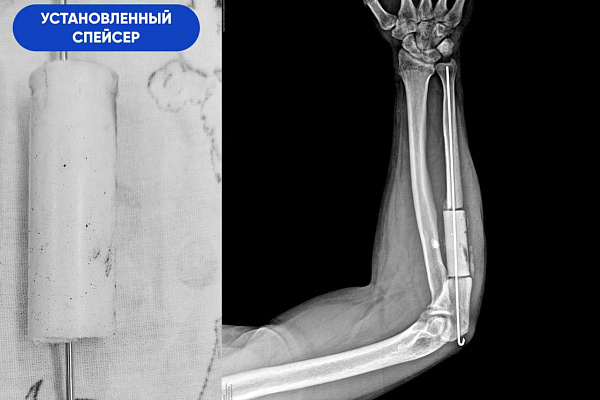

-После удаления временного имплантата мы пересадили в предплечье донорскую часть. Необходимые 8 сантиметров взяли из малоберцовой кости* и зафиксировали аутотрансплантат специальной накостной пластиной. Таким образом, весь запланированный объём хирургической работы был выполнен. Последняя операция прошла штатно. Но нужно понимать, что приживление костного блока – это сложный и длительный процесс, который сопровождается угрозой отторжения. Со своей стороны мы сделали всё от нас зависящее, чтобы этот период прошёл благополучно. Все управляемые риски нами учтены и сведены к минимуму, - отмечает Сергей Глиняный.

*Голень состоит из двух костей – опорной большеберцовой и не опорной малоберцовой. Забор трансплантата из малоберцовой кости не повлияет на функцию ноги и качество жизни пациента.